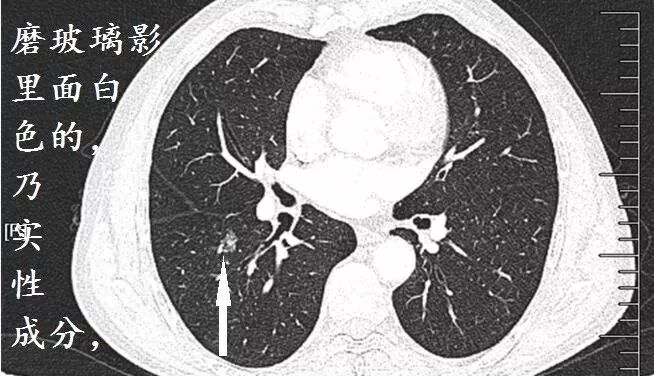

下面这个是什么?

首先,磨玻璃影,很可能是癌;假如里面有高密度的实性成分,则更可能是癌,并且,接近100%是腺癌

假如病理科报道:鳞癌。你可以要求病理科做免疫组化,再看看片子,不要冲动